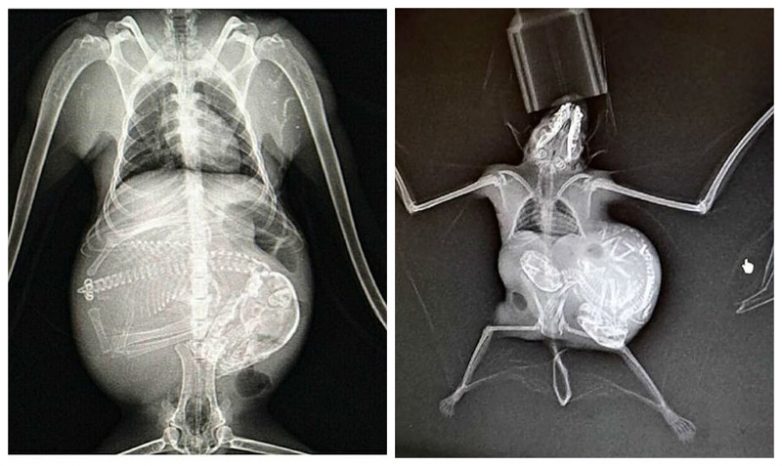

Беременность животных на рентген-снимках

Представляем вашему вниманию серию интересных рентгеновских снимков, на которых можно рассмотреть, как располагаются будущие детеныши енота, летучей мыши или, скажем, бородатой ящерицы в животах их мам.

Для некоторых животных вынашивание сразу нескольких детенышей — это норма, а некоторые (например, летучие мыши, мартышки или олени) рожают только одного (летучие мыши могут выносить до трех детенышей, но это редкость). Что касается длительности вынашивания, то самая короткая беременность — у опоссумов (12-13 дней), а самая длительная — у слонов (20-22 месяца).

Мунтжак (небольшой олень)

Французский лангур (мартышка)